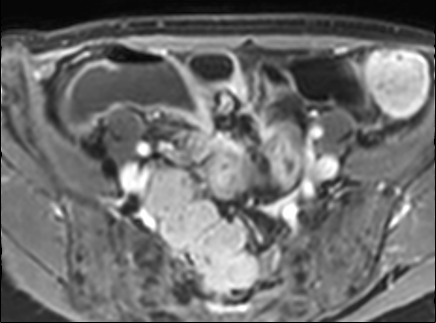

Thâm nhiễm

Thâm nhiễm có thể biểu hiện dưới dạng mỡ bò (creeping fat) xâm lấn giữa các quai ruột kèm thay thế tín hiệu mỡ bình thường, cùng với hiện tượng kéo dính và gập góc các quai ruột.

Các triệu chứng tắc nghẽn do dính ruột, hẹp do viêm hoặc xơ hóa là những biểu hiện thường gặp.

Rò và áp-xe thường đồng thời hiện diện.

Do cấu trúc phức tạp, đường đi chính xác của đường rò có thể khó xác định.